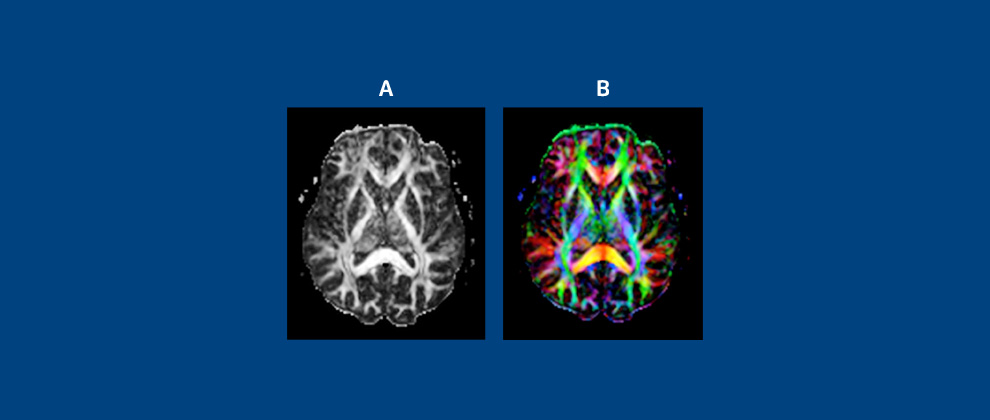

Figura 3: quadros A e B representam, respectivamente, Difusão Tensorial (DTI) e Mapas de Anisotropia Fracionada (AF).

O quadro A, em mapa de AF simples em branco e preto, mostra conexões mais importantes da substância branca encefálica; quadro B, em mapa de cores, mostra a direção dos tratos (azul: crânio caudal; vermelho: transversal; verde: anteroposterior.